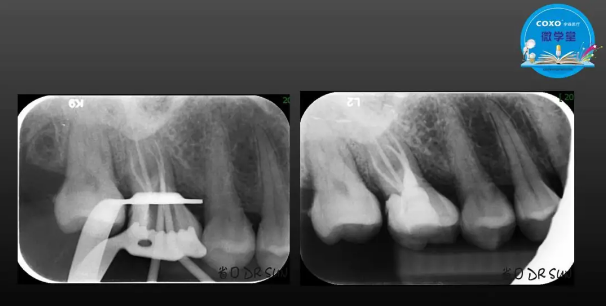

主講:孫書昱

主任醫(yī)師,牙體牙髓副主任, 廣東省口腔醫(yī)院牙體牙髓科 主任醫(yī)師。2003年碩士研究生畢業(yè),研究方向為牙體牙髓病學,擅長于牙體牙髓病的診斷、齲齒、牙髓炎、根尖周病的治療以及前牙美容修復。